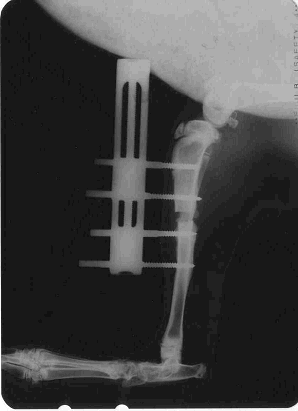

Regeneration of Femur (Thigh bone) of Rabbit upon application of Mebiol Gel (Periosteum intact).